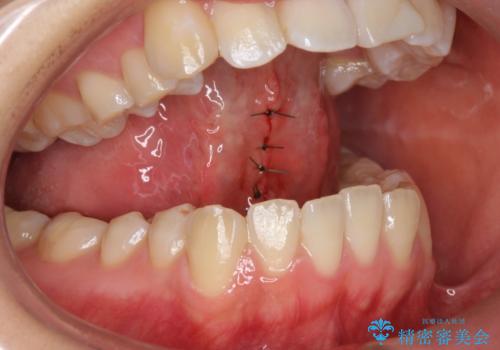

舌が持ち上がらない 舌小帯切除

- 舌小帯の切除を希望して来院。

術後に舌の運動(MFT)を行うことで、退縮の防止になります。

舌を持ち上げた時に、ハート型になるのが適応症です。